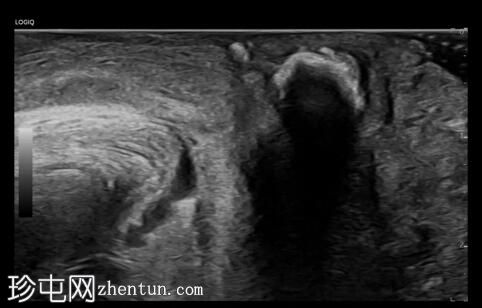

2.jpeg

正位片

放大片

盆腔两侧坐骨棘上方、下方及水平可见多发小片状高密度影。尿道及肾区未见明显高密度影。